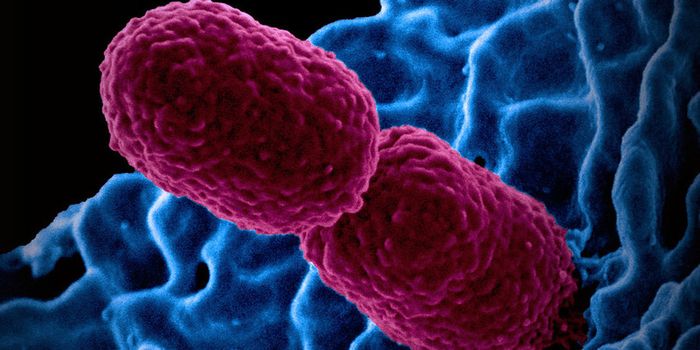

FEB 16, 2025MicrobiologyBacterial pathogens can cause serious infections. So many of them are becoming resistant to the effects of antibiotics t ...

FEB 05, 2025MicrobiologyAntibiotics are a crucial tool in the fight against bacterial infections. But the World Health Organization has long war ...

JAN 26, 2025MicrobiologySepsis is a life-threatening condition that can occur when the body is trying to fight an infection. Now scientists know ...

JAN 07, 2025MicrobiologyBacterial cells have lots of interesting abilities. They can pass a kind of memory onto offspring; easily share genes; a ...